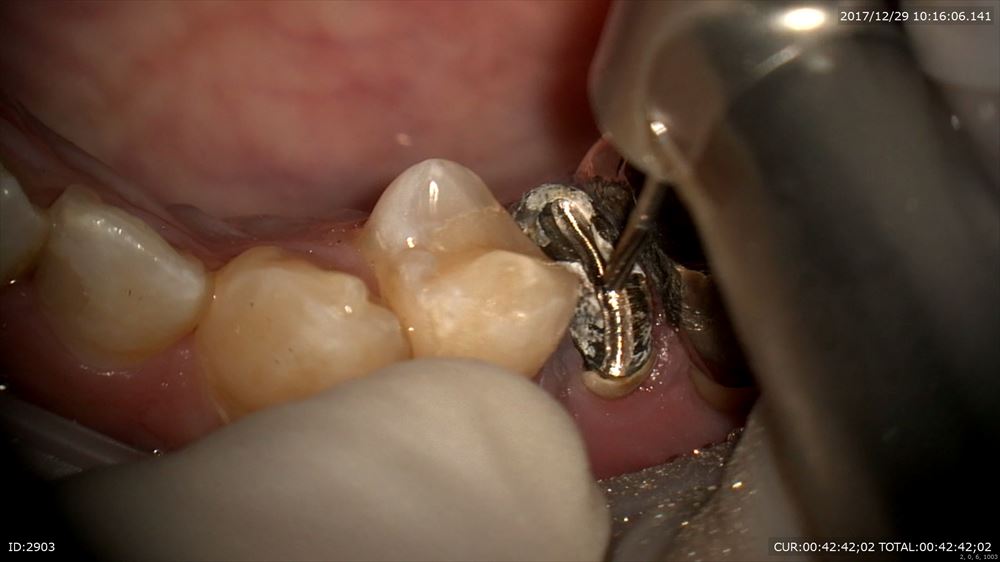

根管充填

CTでも近遠心で確認